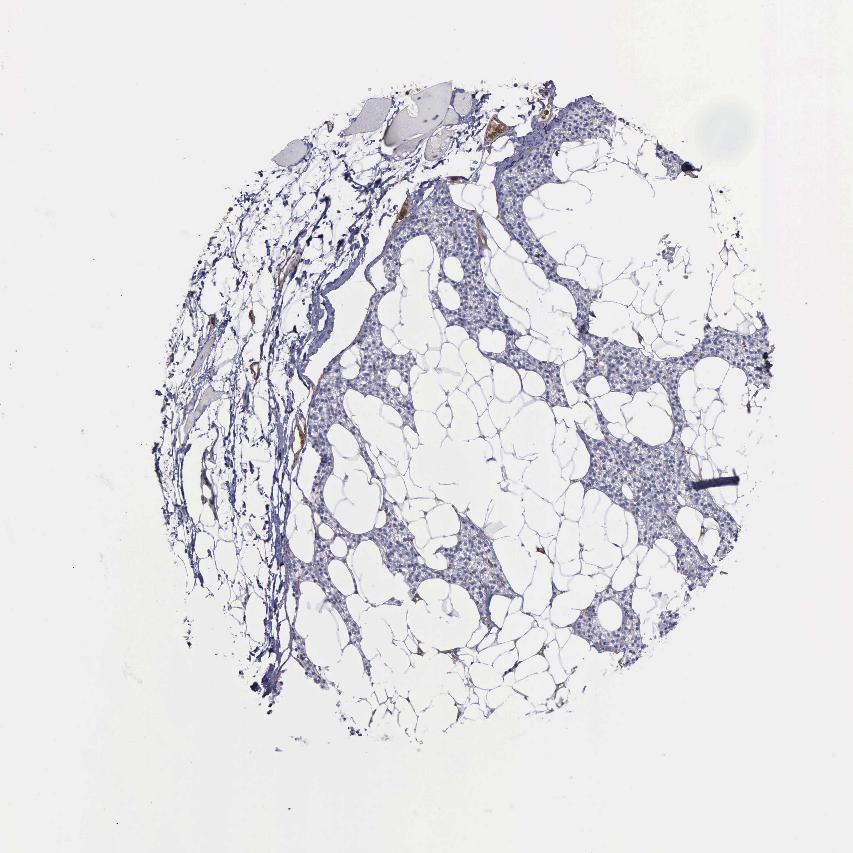

SKELETAL MUSCLE - Antibody stainingi

Antibody staining in the annotated cell types in the current human tissue is reported as not detected, low, medium, or high, based on conventional immunohistochemistry profiling in selected tissues. This score is based on the combination of the staining intensity and fraction of stained cells.

Each image is clickable and will lead to virtual microscopy that enables deeper exploration of all samples and also displays staining intensity scores, fraction scores and subcellular localization as well as patient and tissue information for each sample.

Antibody HPA001115Antibody HPA002925Antibody CAB000356

Myocytes Not detectedNot detectedNot detected